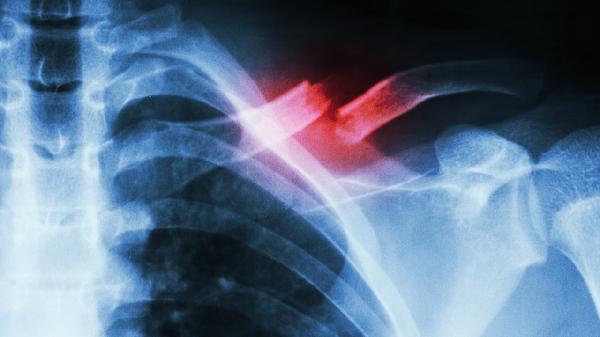

锁骨骨折恢复期需建立均衡膳食模式,除上述重点营养素外,还应保证新鲜蔬果摄入以提供抗氧化物质。避免高盐、高糖及含磷碳酸饮料影响钙代谢,戒烟限酒以防血管收缩阻碍愈合。餐后适当活动促进消化吸收,但需避免患侧负重。定期复查X线观察骨痂生长情况,若出现愈合延迟需在医生指导下调整营养方案。睡眠时保持患肢功能位,配合医嘱进行渐进式康复训练,营养与运动结合可显著提升恢复效果。